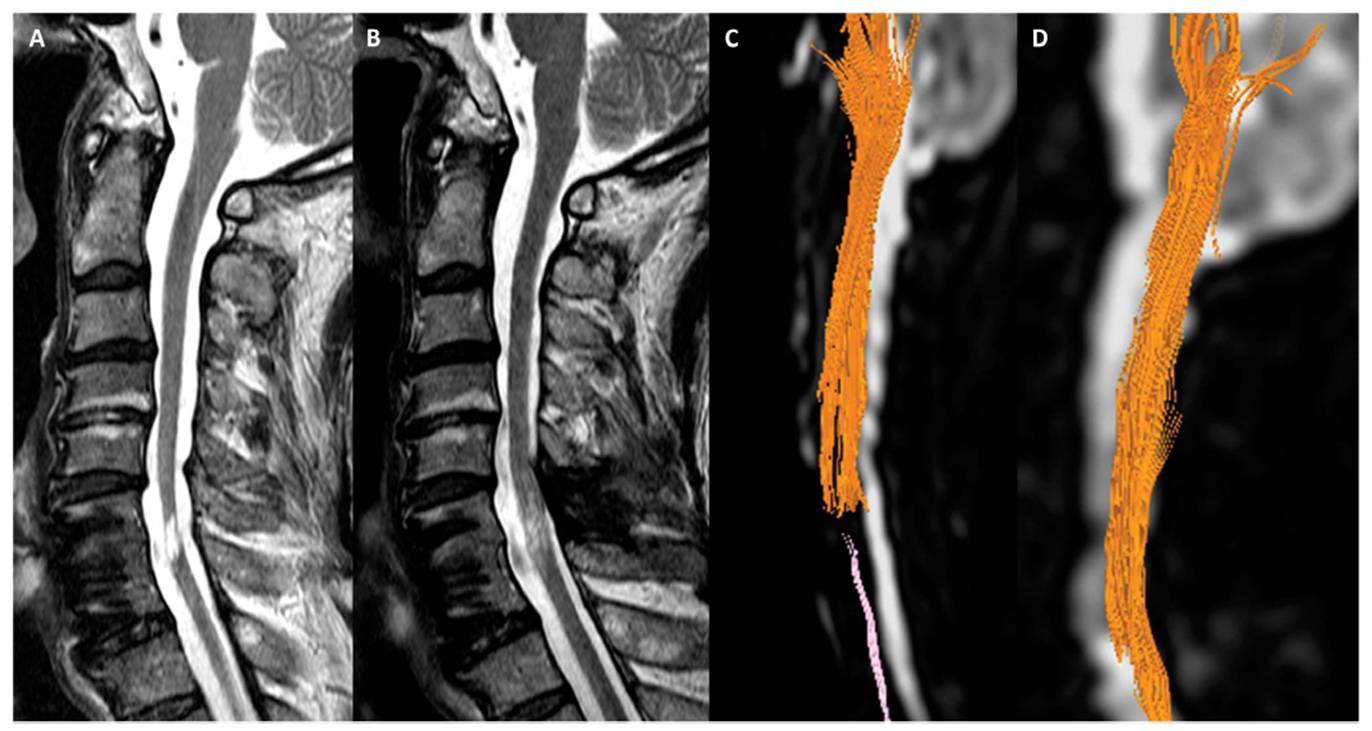

이어 “그러나 줄기세포치료제를 단회 투여했음에도 불구하고 호전된 환자의 척수 MRI 및 DTI 검사 결과 척수손상 부위에서 줄기세포치료 전에는 없던 섬유의 연속성(fibercontinunity)이 확인되는데 이는 줄기세포치료로 인한 신경재생 효과로 판단할 수 있다"고 말했다.

[환자의 MRI와 DTI검사결과다. 줄기세포치료제투여하기 전(A와C)에 비해 투여 후 6개월이 경과한 후(B와 D)에는끊어진 척수신경이 재생되었음을 확인할 수 있다.]